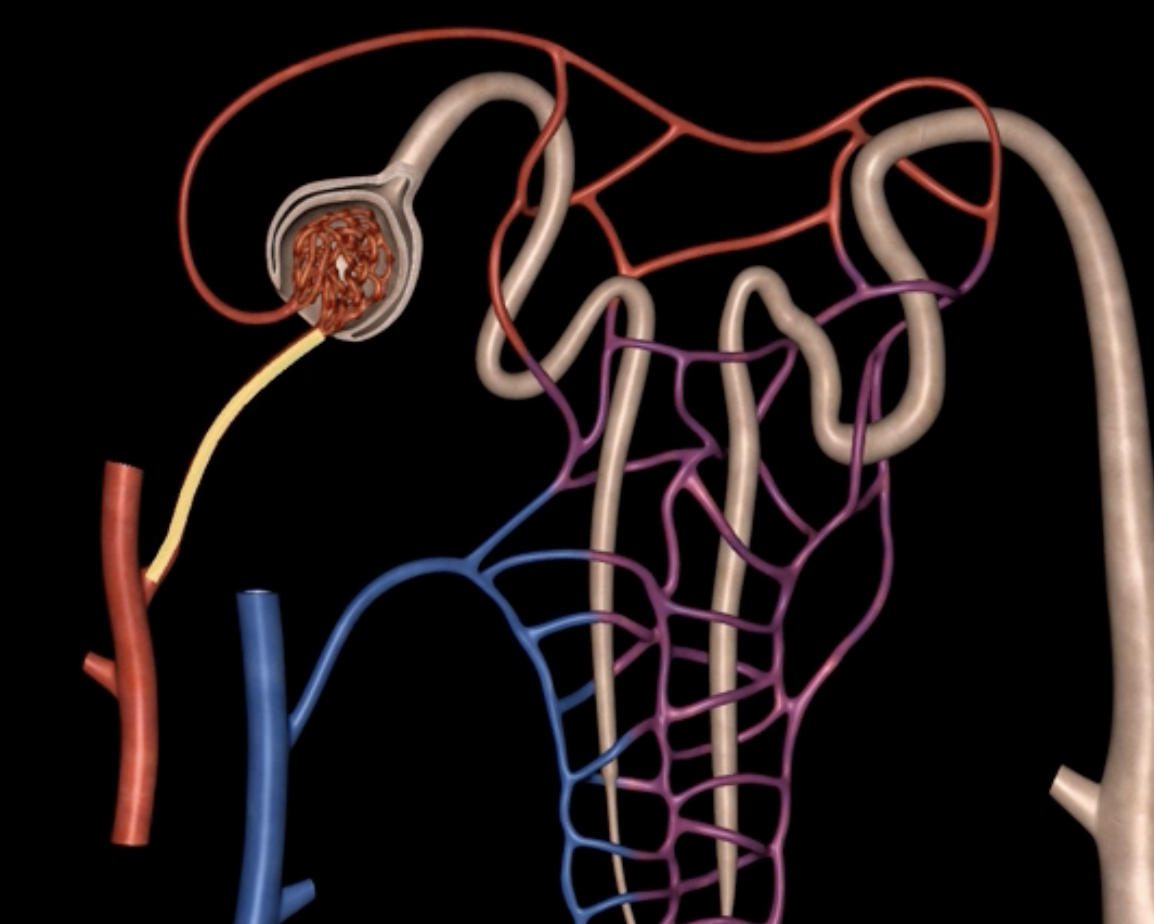

afferent arteriole

yellow

glomerulus

green

efferent arteriole

purple

orange: peritubular capillaries

green: vasa recta

efferent arteriole give rise to orange and green

yellow: cortical nephron

blue: juxtamedullary nephron

yellow:

blue: